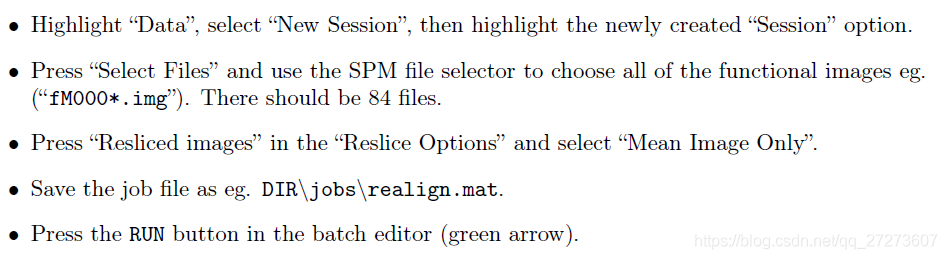

2.1Realignment对数据进行重新排列

然后matlab输入SPM,点击fmri。按照以下步骤进行,

运行完程序后,matlab窗口出现‘Done ‘Realign: Estimate & Reslice’’。然后得到两个结果,记录受试者的头动情况。